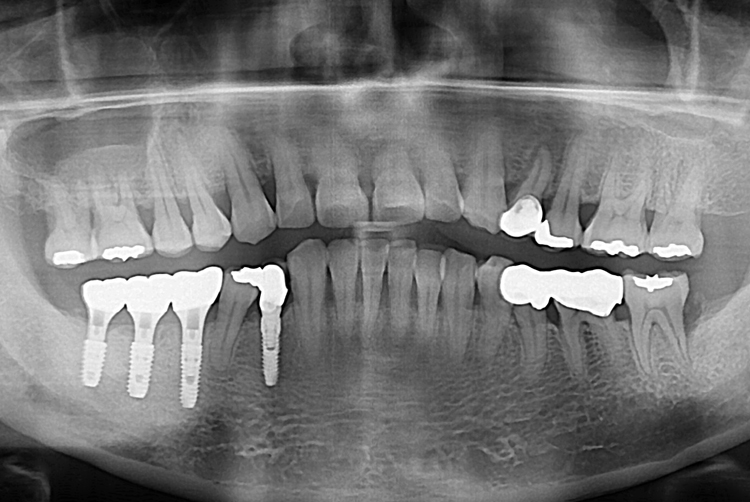

[임플란트] 어금니 임플란트

치료전 : 2017-07-17

세종치과는 많은 환자와 다양한 케이스를 바탕으로

항상 편안한 임플란트 수술을 제공하고자 노력하고,

오래동안 튼튼히 쓸 수 있는 임플란트 수술을 가장 큰 목표로 삼고 있습니다.